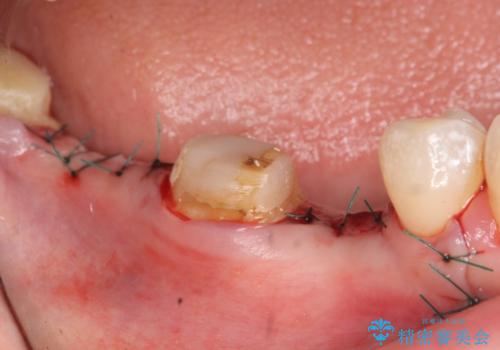

右下7は欠損しており、右下5は保存不可能だったため、インプラントによる欠損補綴を行いました。

インプラント埋入時には骨が不十分な部位に骨増生を行っております。

- オールセラミッククラウン…¥100,000×3、仮歯…¥10,000×3、インプラント(ストローマン)…¥200,000×2、カスタムアバット…¥100,000×2、骨増生…¥50,000費用は治療当時の料金となります